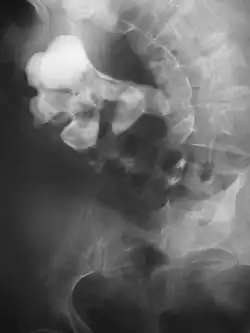

Kidney with calcium deposits and a partially formed stag horn calculus.

Radiograph showing a large staghorn calculus involving the major calyces and renal pelvis in a person with severe scoliosis

Stones less than 5 mm (0.2 in) in diameter pass spontaneously in up to 98% of cases, while those measuring 5 to 10 mm (0.2 to 0.4 in) in diameter pass spontaneously in less than 53% of cases.[85]

Stones that are large enough to fill out the renal calyces are called staghorn stones and are composed of struvite in a vast majority of cases, which forms only in the presence of urease-forming bacteria. Other forms that can possibly grow to become staghorn stones are those composed of cystine, calcium oxalate monohydrate, and uric acid.[86]